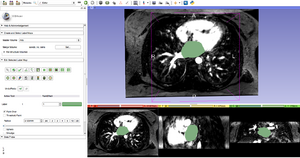

Loading data into Slicer

Segmenting the endo in the MRA

We have been developing an approach to segmentation of cardiac DE-MRI images that uses the associated MRA to help define endocardial boundaries. This approach is possible because CARMA is now acquiring gated MRAs routinely for patients. The approach is to perform a quick, semi-automated segmentation of the LA in the MRA, register the MRA to the DE MRI, and then refine the registered segmentation based on the DE MRI data.

• To design and implement a Slicer module or wizard that walks the user through segmentation of the LA using the MRA in conjunction with the DE MRI